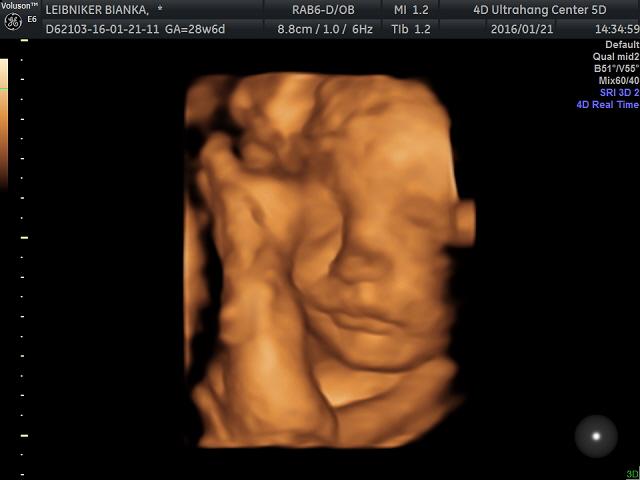

lbianka

Sziasztok!

Véleményeket szeretnék megtudni a Medical 4D Ultrahang centerről (Gólyahír Medical Center Budapest, II. kerület, Török utca 5.). Telefonon egyeztetve elsőre nekem nem volt túl szimpi, és nem tudom, hogy az mennyire normális, hogy egy egyszerű időpontfogalálsért előre elkérnek 3.000 Ft-ot..

Volt valaki már náluk? Megéri a 12.000 Ft-ot a garanciális 4D csomagjuk, ami annyiban garanciális, hogy ha nem látszik a pici 4D-n - mert túl közel van a hasfalhoz (?) - akkor 1 héten belül +3000 Ft-ért megismétlik a vizsgálatot. Picit fura nekem ez. Ez a rendszer a többi rendelőben is? Ez ilyen Babamamatudakozós kuponos ajánlat...